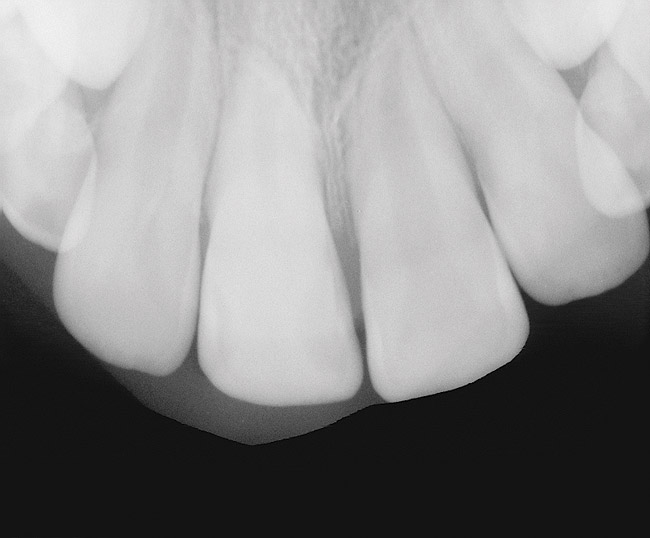

As mentioned, all risk factors associated with both root canal and implant therapy must be carefully considered. Comprehensive clinical and radiographic assessments are necessary to evaluate the patient's risk factors associated with his or her particular case (Figure 1, Figure 2 and Figure 3). The primary risk factors for implants can include smoking, bone quality, and systemic health. For endodontic therapy the primary risk factors are related to the anatomic root complexity, failed root canal treatment with significant technical defects manifested as iatrogenic events, less-than-optimal periodontal status of the tooth (due to a subsequent risk of vertical fracture), and a clinician's lack of experience with regard to the case's complexity. A strong correlation exists between failed root canal treatment and a lack of coronal seal after treatment. This is highly relevant in treatment planning. Often, endodontically treated teeth fail not because they were treated inappropriately and need extraction, but rather, because they have been left unsealed and assaulted by bacteria after the endodontic therapy, causing subsequent long-term clinical failure (Figure 4 and Figure 5).